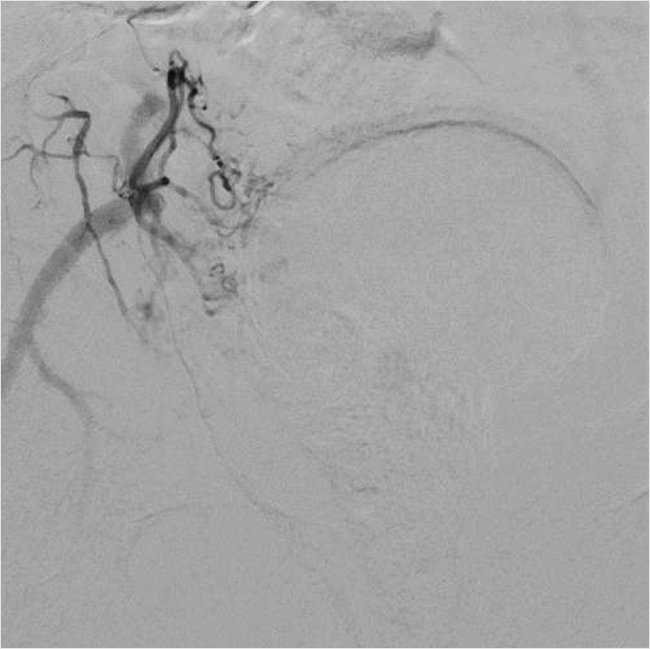

Рисунок 2. Селективная катетеризация простатической артерии справа. Ангиография простатической артерии справа до эмболизации

Для катетеризации простатических артерий по диагностическому проводнику был заменен катетер на диагностический гидрофильный катетер Terumo 4F длиной 150 см и микрокатетер Progreat Lambda 1,9F длиной 175 см с интервенционным гидрофильным проводником 0,014. Микрокатетер избирательно по интервенционному проводнику был поэтапно позиционирован в правой и левой простатической артерии (рис. 3, 5).